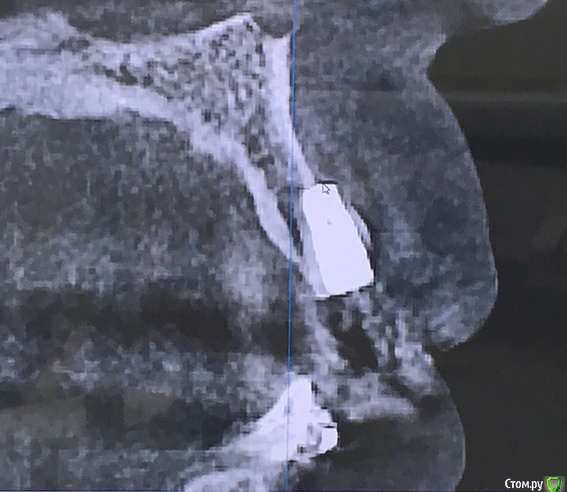

Naminutku Опубликовано 22 марта, 2019 Поделиться Опубликовано 22 марта, 2019 Уважаемые форумчане, прошу вашей помощи в сложившейся ситуации.Сразу отмечу, что нет цели кого-то уличить в непрофессиональности, есть цель разобраться в ситуации и принять правильное решение относительно дальнейшего лечения. Установлено 2 имплантата АльфаБио 3,3х8мм. Один в районе жевательного зуба, второй в зоне резца.По ряду обстоятельств после имплантации я обратилась в другую клинику за консультацией (в обеих клиниках причин сомневаться в профессионализме и добрых намерениях у меня нет)Во время консультации был сделан 3D снимок, на котором видно, что имплантат в районе жевательного зуба не полностью погружен в костную ткань и расположен на 2мм выше края кости. В районе резца имплантат выходит за пределы костной ткани (см. снимки)Врач считает, что в обоих случаях имплантаты установлены некорректно. В районе жевательного зуба в последующем мягкие ткани разрушатся и выступающая часть имплантата будет торчать, а в районе резца очень высока вероятность развития воспаления и разрушения костной ткани, + из-за особенностей позиционирования, коронку придется делать со смещением (т.е. центральные оси коронки и имплантата не будут совпадать), что вместе приведет к недолговечности всей этой истории. Предложения 2:1. оставить как есть, закончить лечение и решать проблемы по мере возникновения.2. пока имплантаты не успели намертво врасти в кость (срок чуть больше месяца), убрать, восстановиться и поставить новые имплантаты.Мне очень важно мнение профессионалов в данной ситуации. Насколько критична ситуация, стоит ли удалять, заново имплантировать или проблемы с существующими имплантатами нет? Ссылка на комментарий

red_butler Опубликовано 22 марта, 2019 Поделиться Опубликовано 22 марта, 2019 Ничего критичного я на снимках не увидел... Ссылка на комментарий

koreandr Опубликовано 22 марта, 2019 Поделиться Опубликовано 22 марта, 2019 Тоже ничего критичного не вижу Ссылка на комментарий

suballex Опубликовано 25 марта, 2019 Поделиться Опубликовано 25 марта, 2019 Плюсую. На данный момент, критических изменений нет. Ссылка на комментарий